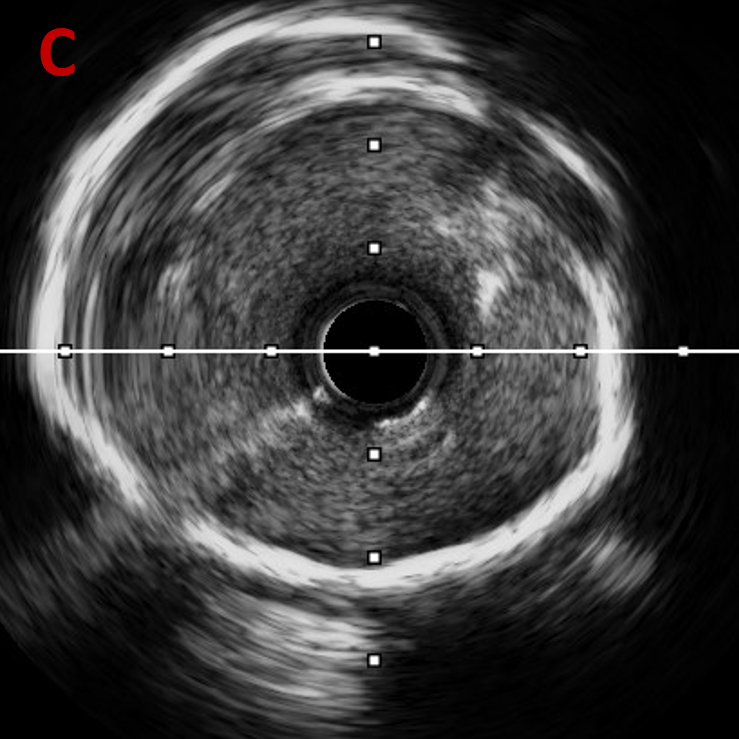

PCI术后IVUS

IVUS提示:后扩张处理后支架膨胀、贴壁良好